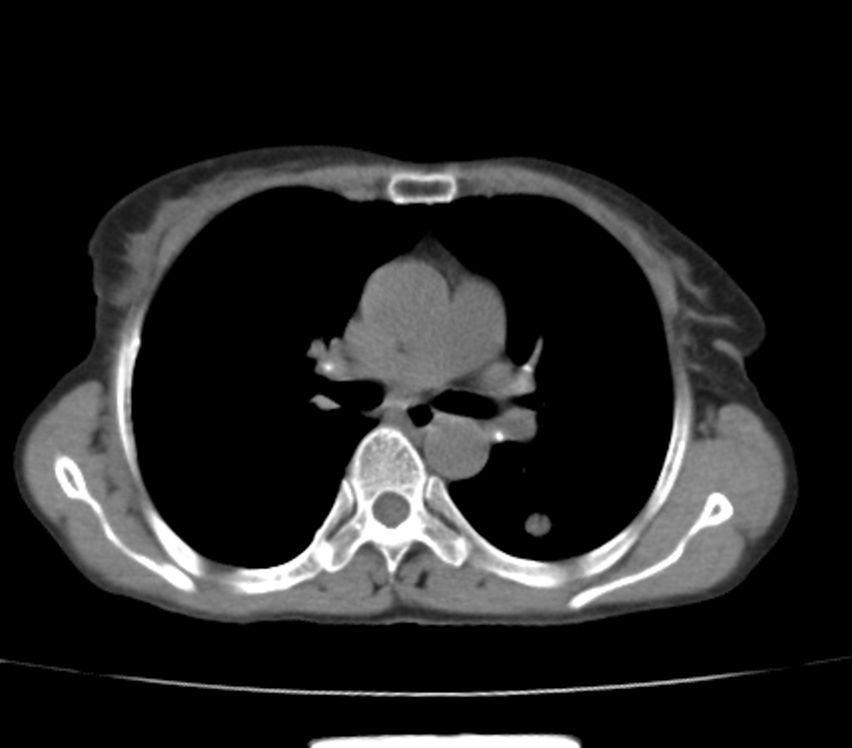

标题: CT21609:右乳包块1年,请各位讨论分析一下,乳腺CA, [打印本页]

标题: CT21609:右乳包块1年,请各位讨论分析一下,乳腺CA,

考虑---右乳癌并胸壁、肋骨、双肺转移。

考虑乳腺癌侵犯肋骨、胸壁及两肺转移可能性大。

右乳癌并胸壁、肋骨、双肺转移。

考虑右侧乳腺癌侵犯肋骨、胸壁及两肺转移。

支持考虑---右乳癌并胸壁、肋骨、双肺转移。

考虑右侧乳腺癌侵犯肋骨、胸壁及两肺转移可能。

考虑右侧乳癌并胸壁、肋骨及双肺多发性转移。